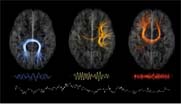

neurologyתסכול בקרב החוקרים ב- McGill University’s Montreal Neurological Institute-MNI and Hospital in Canada   מאיטיות ביישום מעשי של המחקר בתחום מדעי המוח הוליד לאחרונה יוזמה מבורכת בתחום הגישה הפתוחה לנתוני המחקר.

החל משנה זו חוקרים ואנשי סגל במוסד הביעו מחויבות לפרסם בגישה פתוחה את נתוני המחקר , נתונים , תוכנות  ואלגוריתמים ולבקש מעמיתים ממוסדות  מחקר  אחרים לנהוג באופן דומה .כמו כן המוסד לא יבקש פטנטים על הפיתוחים/תגליות  שלו שכן  הקו המנחה הוא: